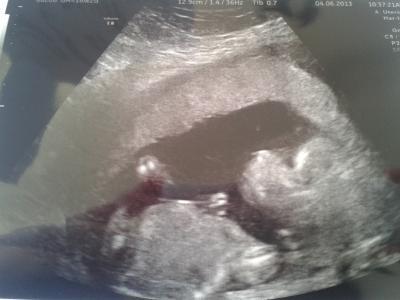

Hallooo bin wieder zurück und es wird wohl ein jungeeee Alles in ordnung. Herz schlägt super. Kopf ist zeitgerecht groß. Mit beinchen ist er nun 21 cm groß. Donnerstag habe ich ein Termin zur feindiagnostik. Sie meinte sie schickt alle hin damit man früh fehlbildungen am herzen erkennen kann. Naja das heißt wieder baby tv fur ca 30 min *freu* Vllt bekommen die ja ein 3D bild hin. Eben hat er uns genau angeschaut und ein profilbild war schwer. Er hat aber den Mund auf und zu gemacht und genuckelt. Er lag ganz still. Hehe sons fühlt sich das immer an als wenn er schonmal Fußball spielen übt Soo wünsche euch einen sonnigenTag, wie hier im Norden Lg

Bild zu FA termin und outing - Forum für November - Mamis